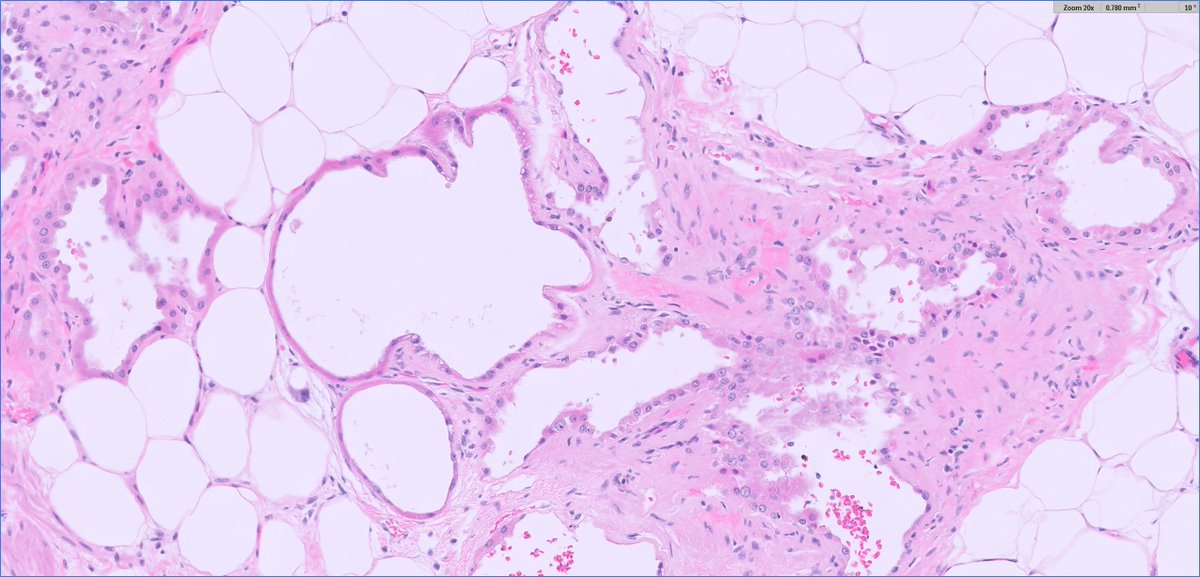

50 y.o. F, radical nephrectomy. What is your diagnosis? Gross photo in the chat. #PathTwitter Mass General Brigham Pathology MGH Pathology